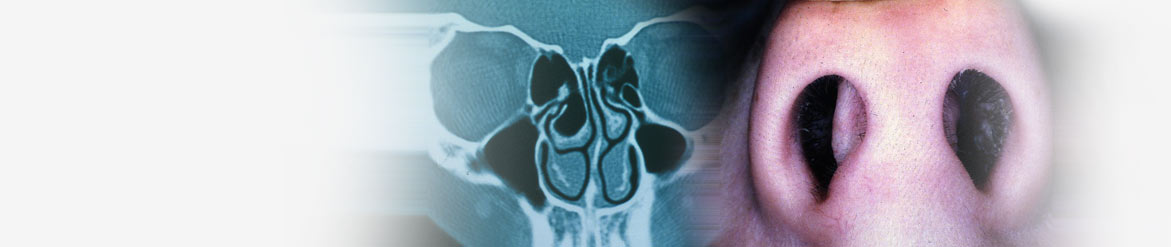

A septoplasty (or sub-mucus resection) is an operation designed to straighten a bend in the septum of the nose. The septum is the midline partition within the nose.

A bend in the nasal septum is diagnosed by a nasal examination and is not usually visible externally. Occasionally, however, the septum under the tip of the nose may be bent into one nostril. This will be visible from the outside.

The commonest problem resulting from a bent septum is a blocked nose. Occasionally, this may cause a twist in the external shape of the nose as well. A bent septum may predispose some people to have chronic sinus problems.